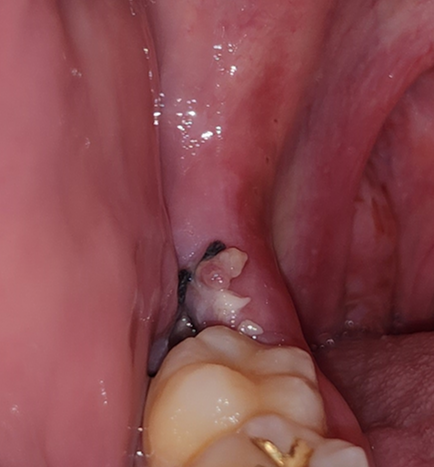

사랑니 발치 4일차입니다. 정상적으로 아물고 있는건지 궁금합니다.

대각선으로 돌출되어있던 아랫 사랑니 발치 4일차입니다.

사진처럼 거무스름한 부위와 흰색으로 염증처럼 보이는 부분이 있는데 따로 조치할 필요가 있을지 궁금합니다.

또 사랑니 발치 후 아랫잇몸이 앞니쪽까지 조금씩 뻐근한 느낌이 드는데 자연스러운 현상인지도 궁금합니다.

• 1번 째 사진

사진으로만 봤을 경우에는 큰 문제가 없이 치유가 되고 있는 것으로 보입니다.

사진상으로는 잘아물고 있는 것으로 보이며, 특별한 조치는 하지 않아도 괜찮습니다. 해당부위에 염증이 덧나지 않도록 헥사메딘 가글액으로 가글하여 관리하길 권합니다.

사진에 보이는건 잇몸이 치유되면서 자연스럽게 나타나는 현상이니 너무 걱정은안하셔도 될것같습니다.

뻐근한느낌은 생길 수 있는 증상이므로 걱정하지 않으셔도 되고 사진상 잘 낫고 있어 보입니다.